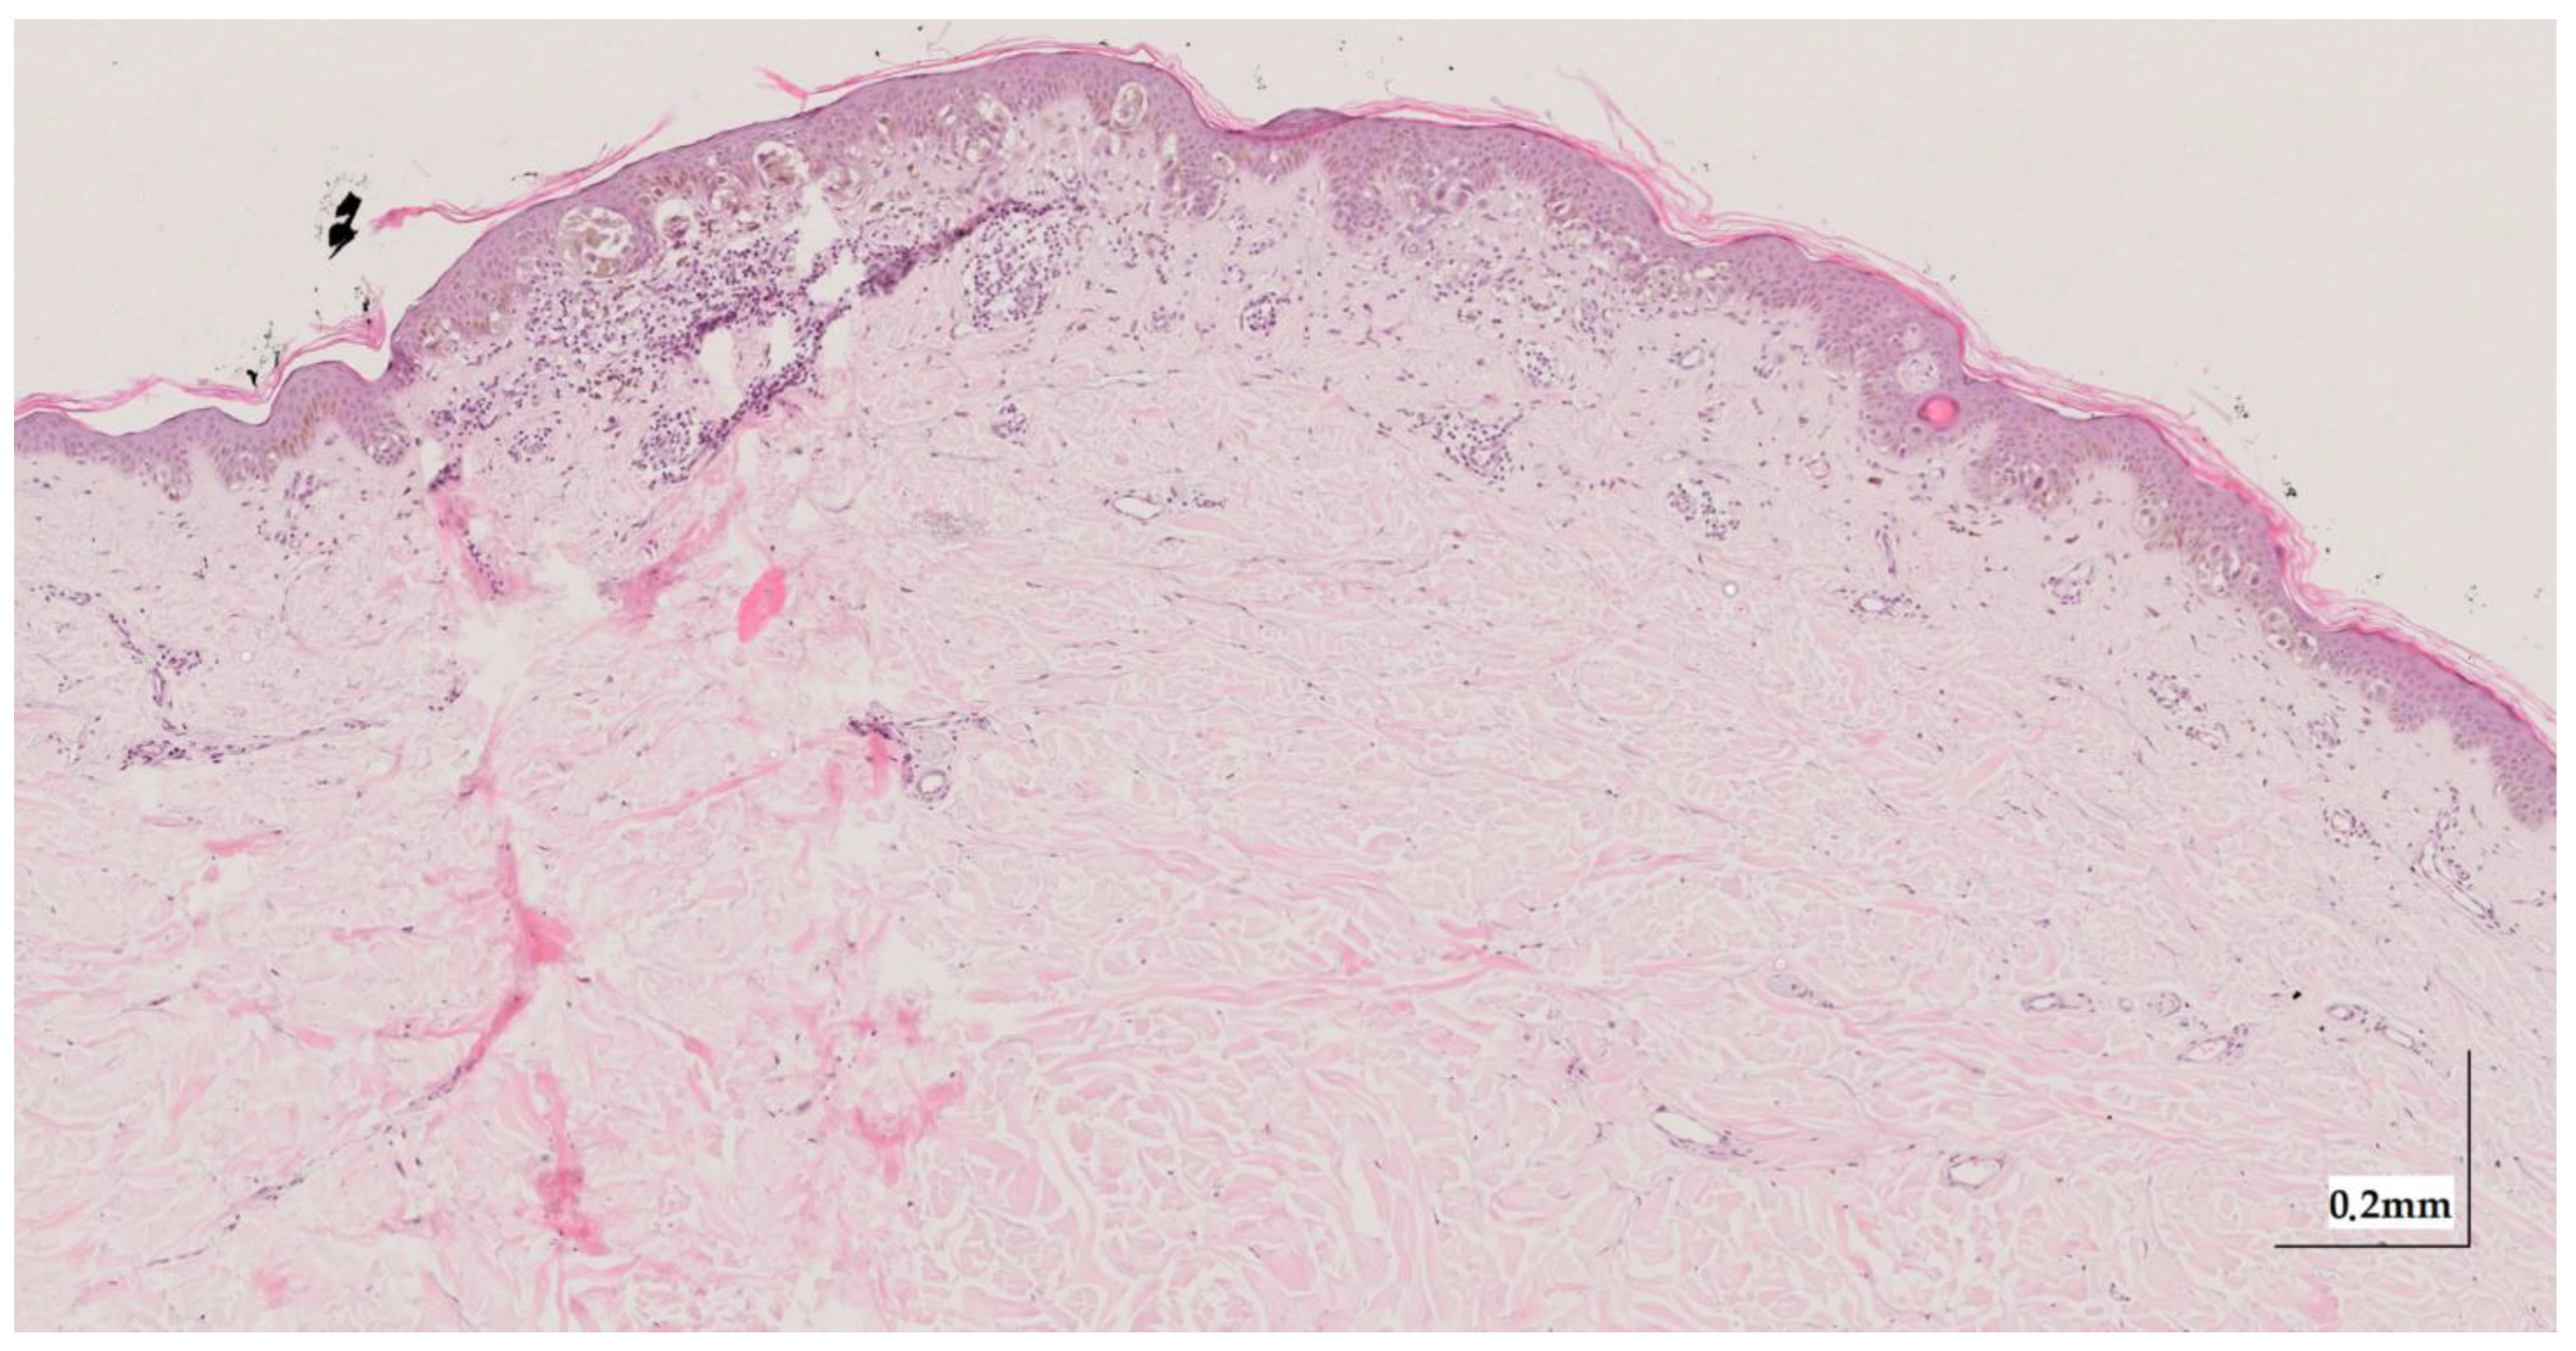

Appendix A. Selected Cases Studies’ HE Histopathological Images (Limited to OCT FOV)

| Superficial spreading melanoma (SSM) Case 1 | Localization: right anterior arm |

![]() | ![]() |